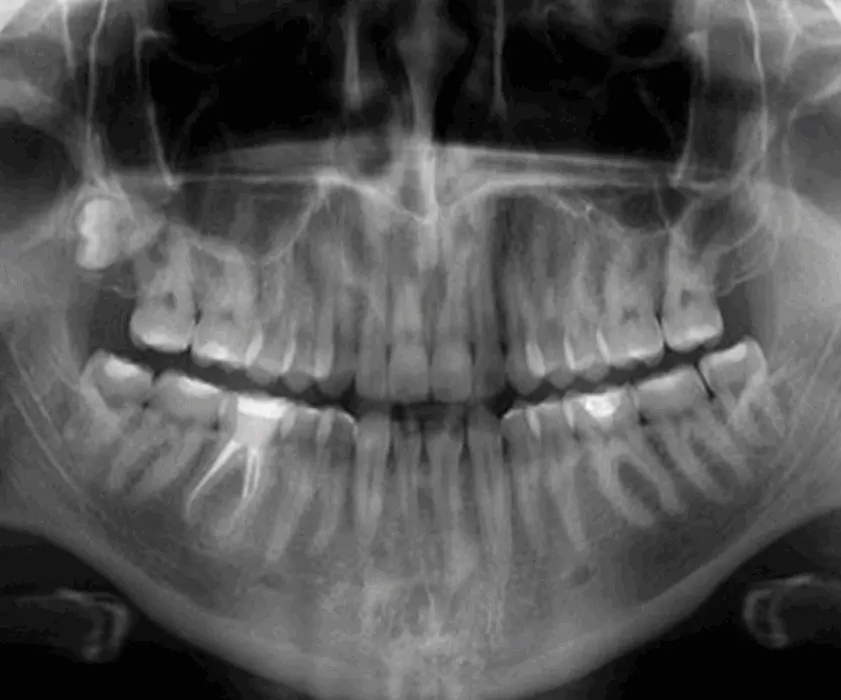

Mit der Panorama-Aufnahme kann der Zahnarzt sehr schnell die Ursache der Schmerzen und Schwellungen erkennen und, der Diagnose entsprechend, eine passende Behandlungsart vorschlagen.

Zahnzysten sind mit Gewebe belegte Hohlräume, die in der Zahnkiefer oder im Weichgewebe auftreten können (z. B. in den Wangen). Zahnzysten entstehen als Folge einer ständigen Infektion, die an der Spitze der Wurzel erscheint. Infizierte Zähne treten in der Regel aufgrund der schlechten Mundhygiene oder aufgrund der nicht rechtzeitigen Behandlung von Karies auf. In letzter Zeit redet man auch von genetischer Vererbung, als der Ursache der Zahnzysten und verschiedenen angeborenen Syndrome.

Wenn eine von diesen Veränderungen diagnostiziert wird, ist es notwendig, so rasch wie möglich, die Veränderung zu entfernen, um zu verhindern, dass sie weiter wachst und sich auf die anderen Zähne verbreitet. Wenn die Veränderung nicht behandelt wird, kann die Zahnstruktur abschwächen, den gesunden Zähnen schaden, Sinus und Nase beeinflussen und große Entzündungen auf dem Gesicht verursachen. Die Zystektomie wird unter örtlicher Betäubung durchgeführt, was bedeutet, dass die Operation für den Patienten völlig schmerzlos ist. Der Oralchirurg entfernt die Zyste vollständig, verkürzt die Wurzelspitze und schließt die Zahnkanäle während der Operation. Wenn die Zyste einen größeren Teil der Wurzel angegriffen hat, dann ist es notwendig, den Zahn zu extrahieren und die Zyste zu entfernen. Eine Woche nach der Operation werden die Nähte entfernt.